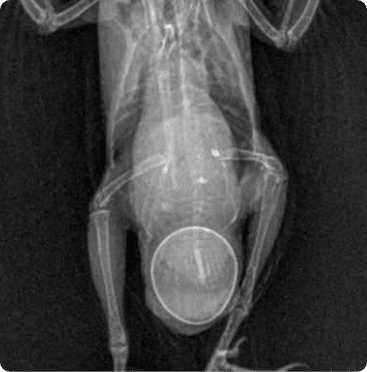

피부질환, wet tail 같은 소화기 문제의 내과질환부터

햄스터 자궁축농증 수술, 종괴제거 수술, 알막힘 등 다양한 질환을 치료합니다.